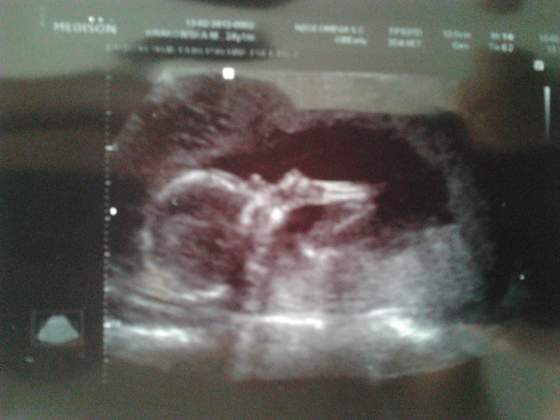

My po usg genetycznym. Dzidzia zdrowa jak ryba, bedzie CHŁOPAK!!!

Co prawda liczyłam na dziewczynke, ale sie ucieszyłam, jak usłyszałam, ze chłopak. Ja chyba nie umiałabym dzewczyny wychować. Mdli mnie na mysl o różowych ubrankach i lalkach ;-) Bedzie Antoś